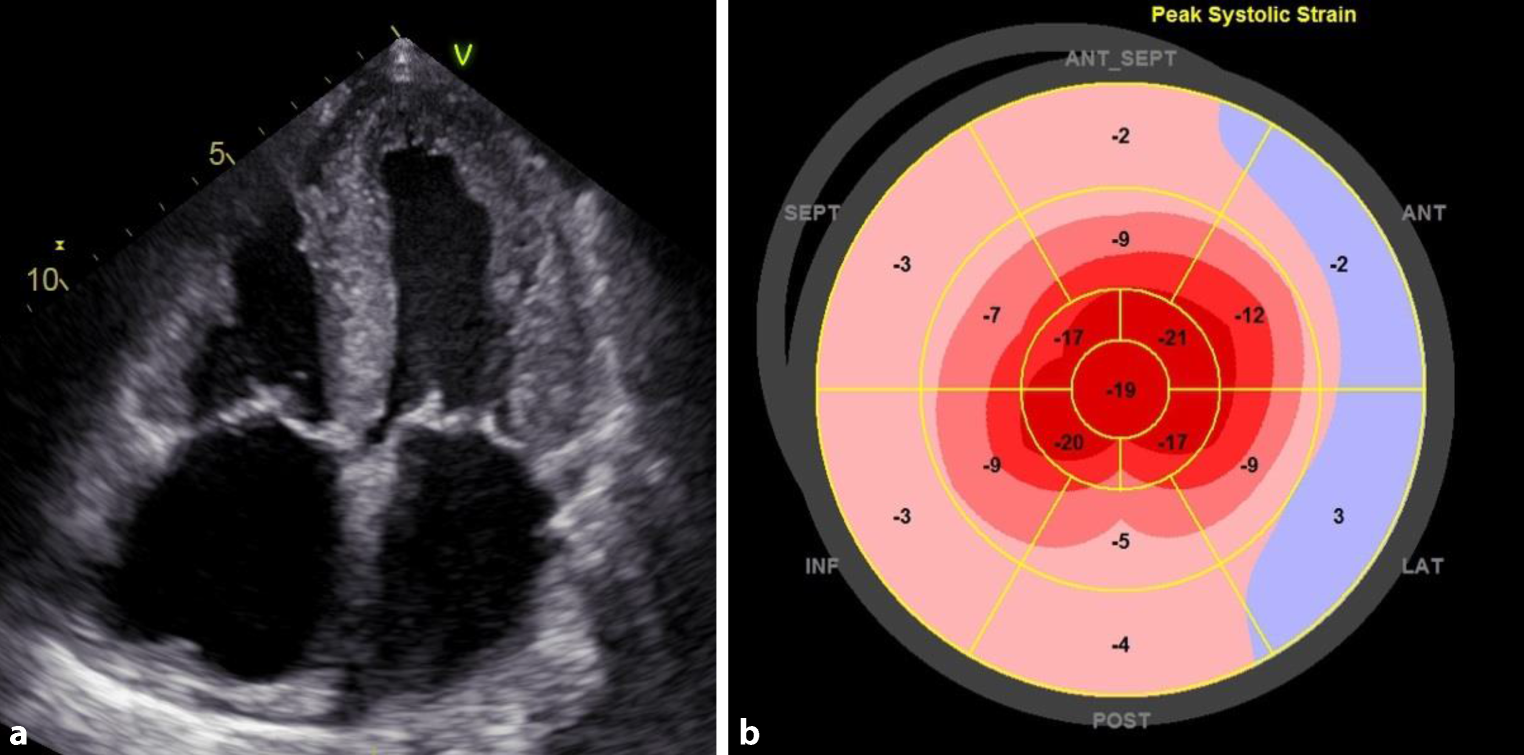

Characteristic echocardiographic findings can contribute to rapid diagnosis. Small or regularly sized, hypertrophic ventricles, enlarged atria, and pericardial effusion indicate the possibility of cardiac amyloidosis (Fig. 2a).

Fig. 2

Echocardiographic findings in cardiac transthyretin amyloidosis. a Apical four-chamber view showing pronounced thickness of the left and right ventricular walls and the interatrial septum, enlargement of both atria and slight pericardial effusion. b Global longitudinal strain analysis in cardiac transthyretin amyloidosis showing apical sparing as a typical sign (i.e., cherry on the top phenomenon). SEPT septal, ANT anterior, INF inferior, ANT_SEPT anterior septal, LAT lateral, POST posterior

Radial LV function is preserved in most patients with cardiac amyloidosis over extended periods, which means that the LV ejection fraction (LVEF) is preserved or only mildly reduced; however, the longitudinal systolic function as assessed by strain analysis (i.e., global longitudinal strain, GLS) is already diminished at the early stages [56, 57]. Therefore, the LVEF to GLS ratio can be helpful to establish diagnosis [58].

A pattern typically found in patients with cardiac amyloidosis consists of preserved apical strain and decreased strain at the base of the heart as well as in the mid-segments of the myocardium [59]. The resulting apical sparing (i.e., cherry on the top) can be visualized using the bull’s eye plot (Fig. 2b; [60]) or the strain ratio. [5658, 61]. Apical sparing is independent of the extent of wall thickening.